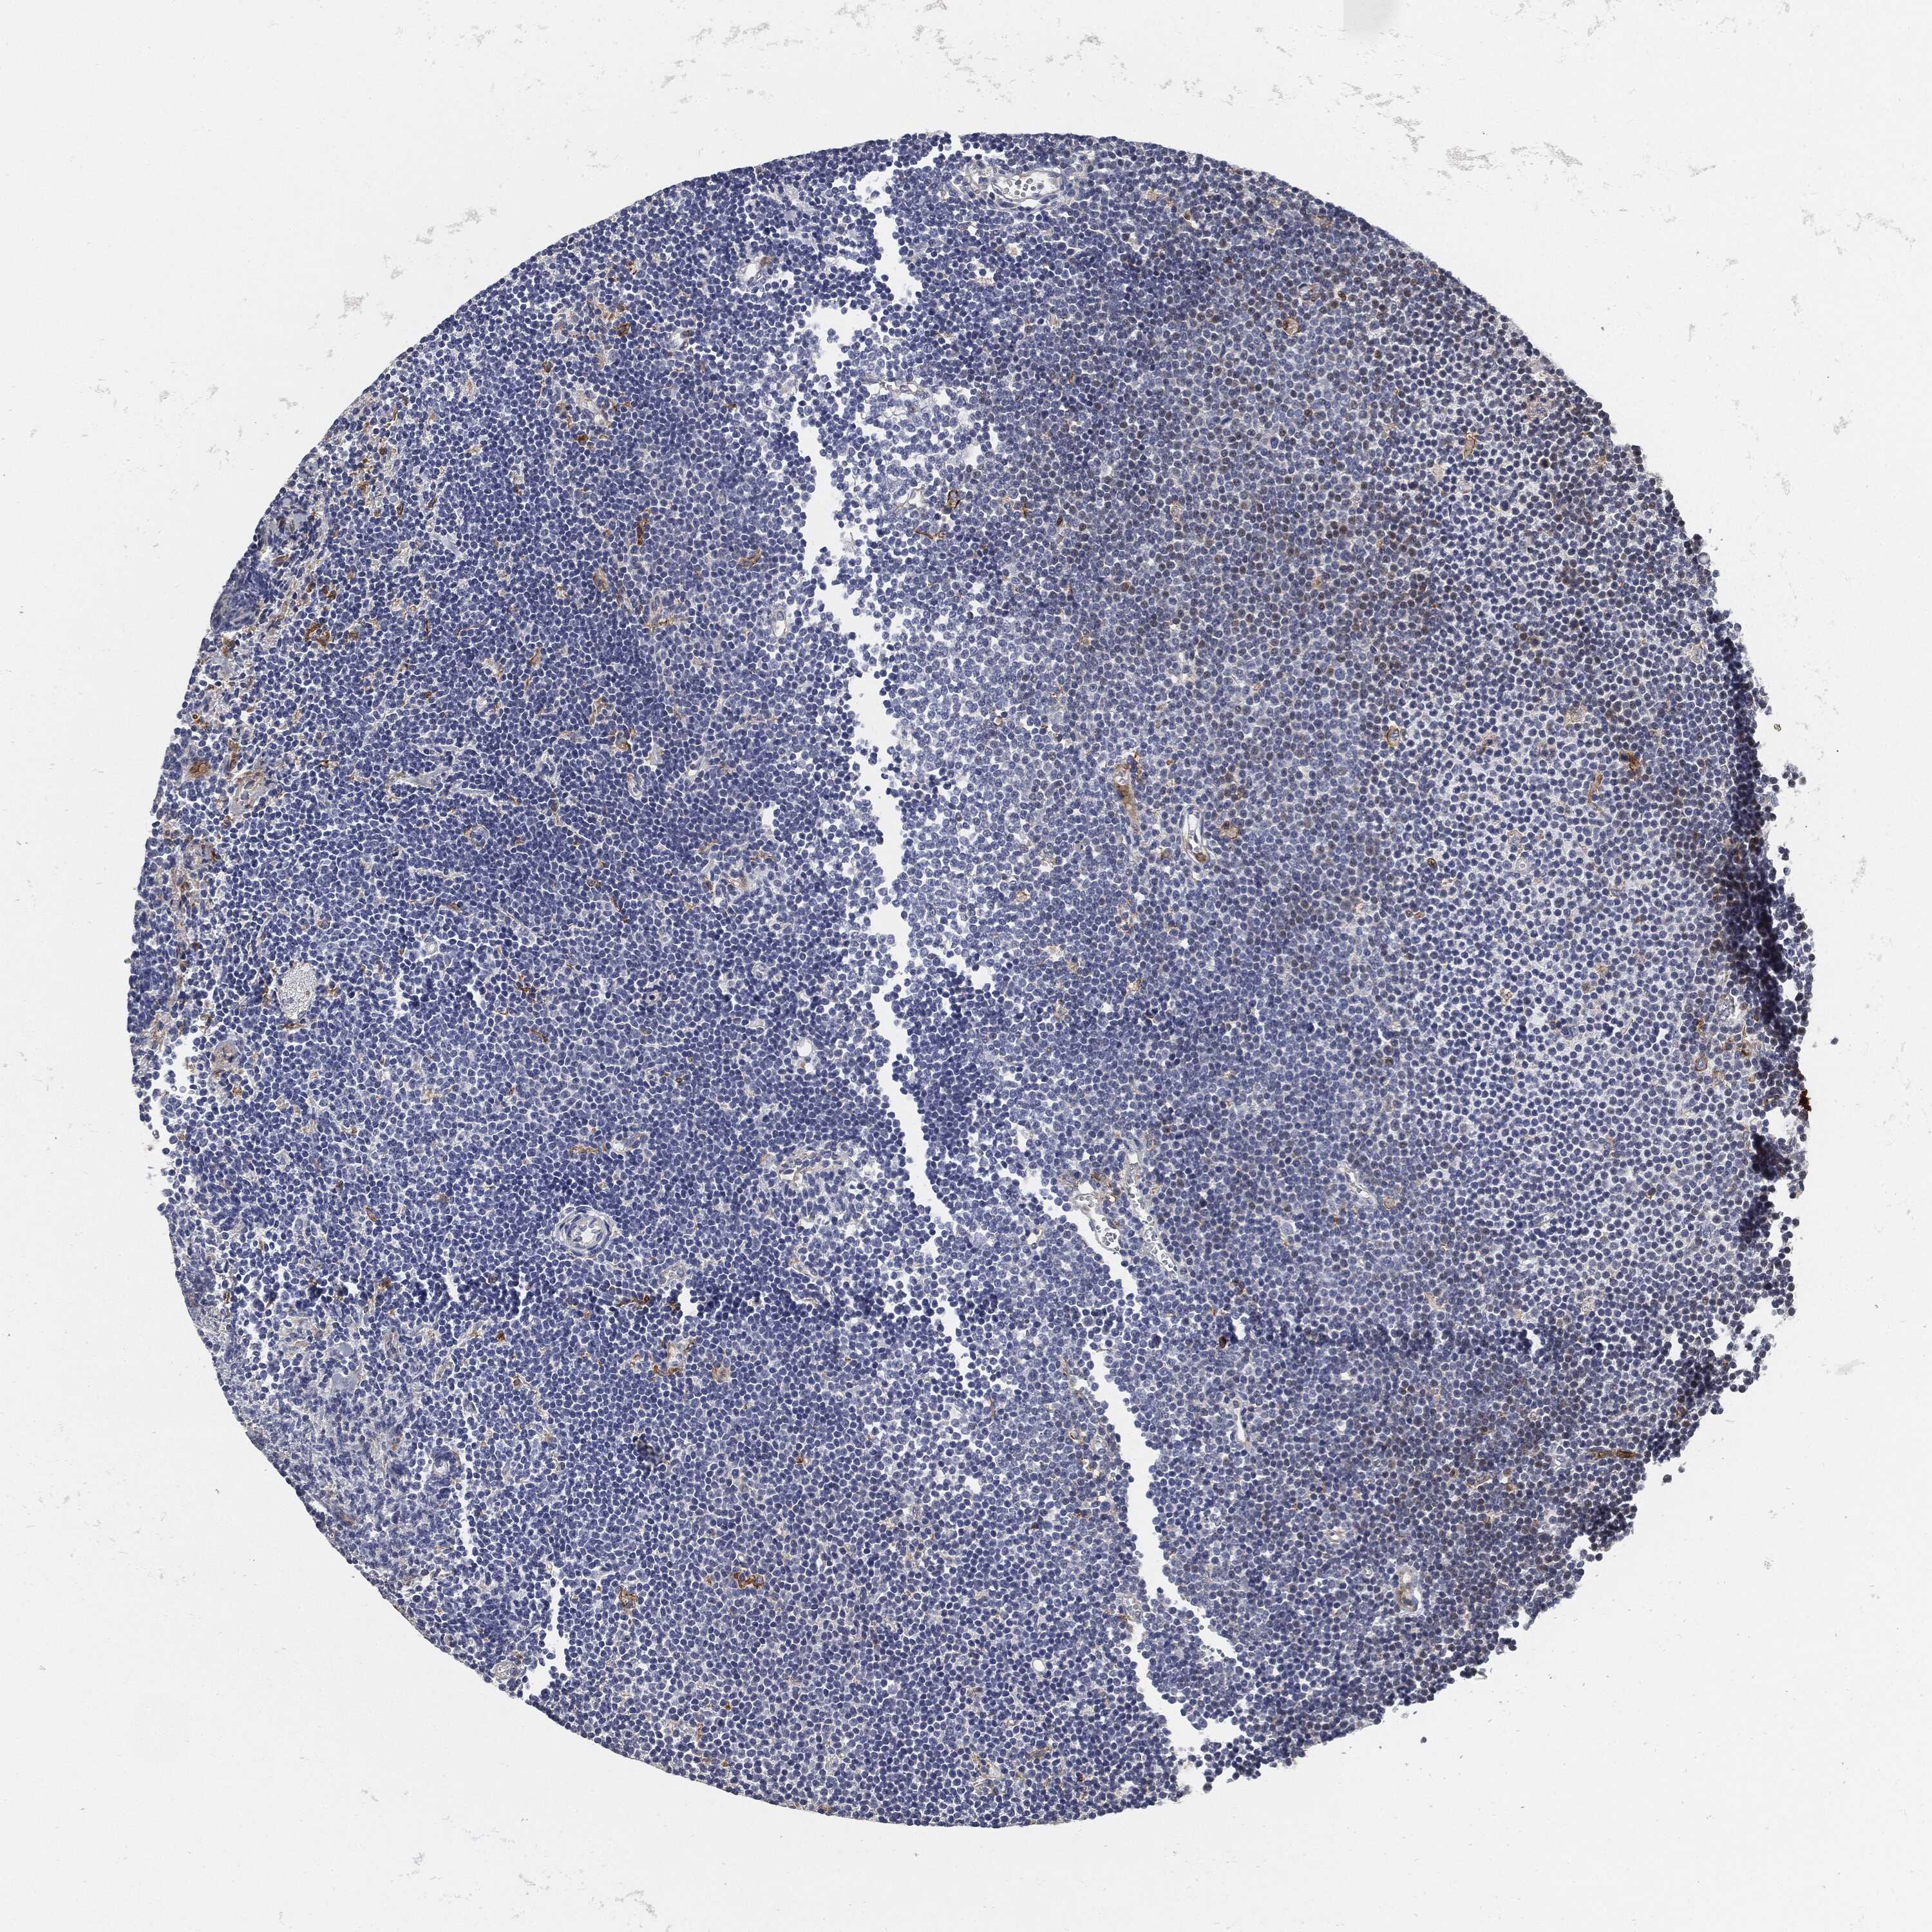

LYMPHOMA - Protein expressioni

A mouse-over function shows sample information and annotation data. Click on an image to view it in a full screen mode. Samples can be filtered based on level of antibody staining by selecting one or several of the following categories: high, medium, low and not detected. The assay and annotation is described here.

Antibody stainingi

Antibody staining in the annotated cell types in the current human tissue is reported as not detected, low, medium, or high, based on conventional immunohistochemistry profiling in selected tissues. This score is based on the combination of the staining intensity and fraction of stained cells.

Each image is clickable and will lead to virtual microscopy that enables deeper exploration of all samples and also displays staining intensity scores, fraction scores and subcellular localization as well as patient and tissue information for each sample.

Antibody CAB080537

Staining

Medium

Moderate

75%-25%

Cytoplasmic/membranous

Malignant lymphoma, non-Hodgkin's type, Low grade

Malignant lymphoma, non-Hodgkin's type, High grade